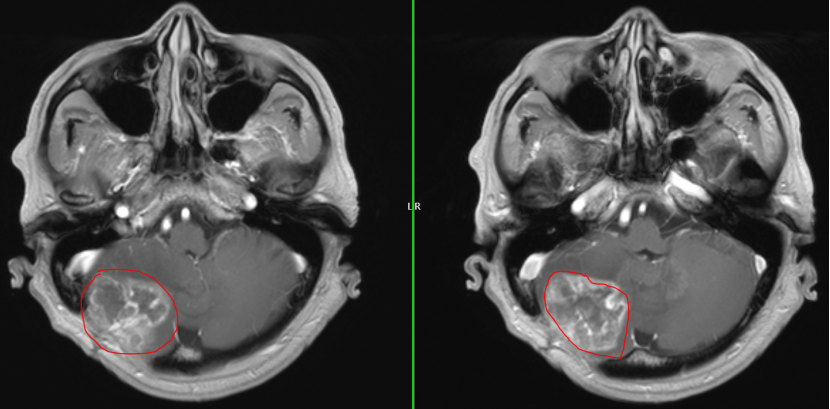

面对如此棘手的局面,周焱峰主任带领团队进行详尽的术前讨论,研读MRI影像,模拟手术入路,为其量身制定手术预案和应急预案。

术前MRI

术后MRI

历时4小时,神经外科团队仔细分离粘连组织,准确找到肿瘤边界,完整切除了复发的肿瘤,术中监测平稳,最大程度地保护了神经功能。手术顺利完成,所有人都松了一口气.。